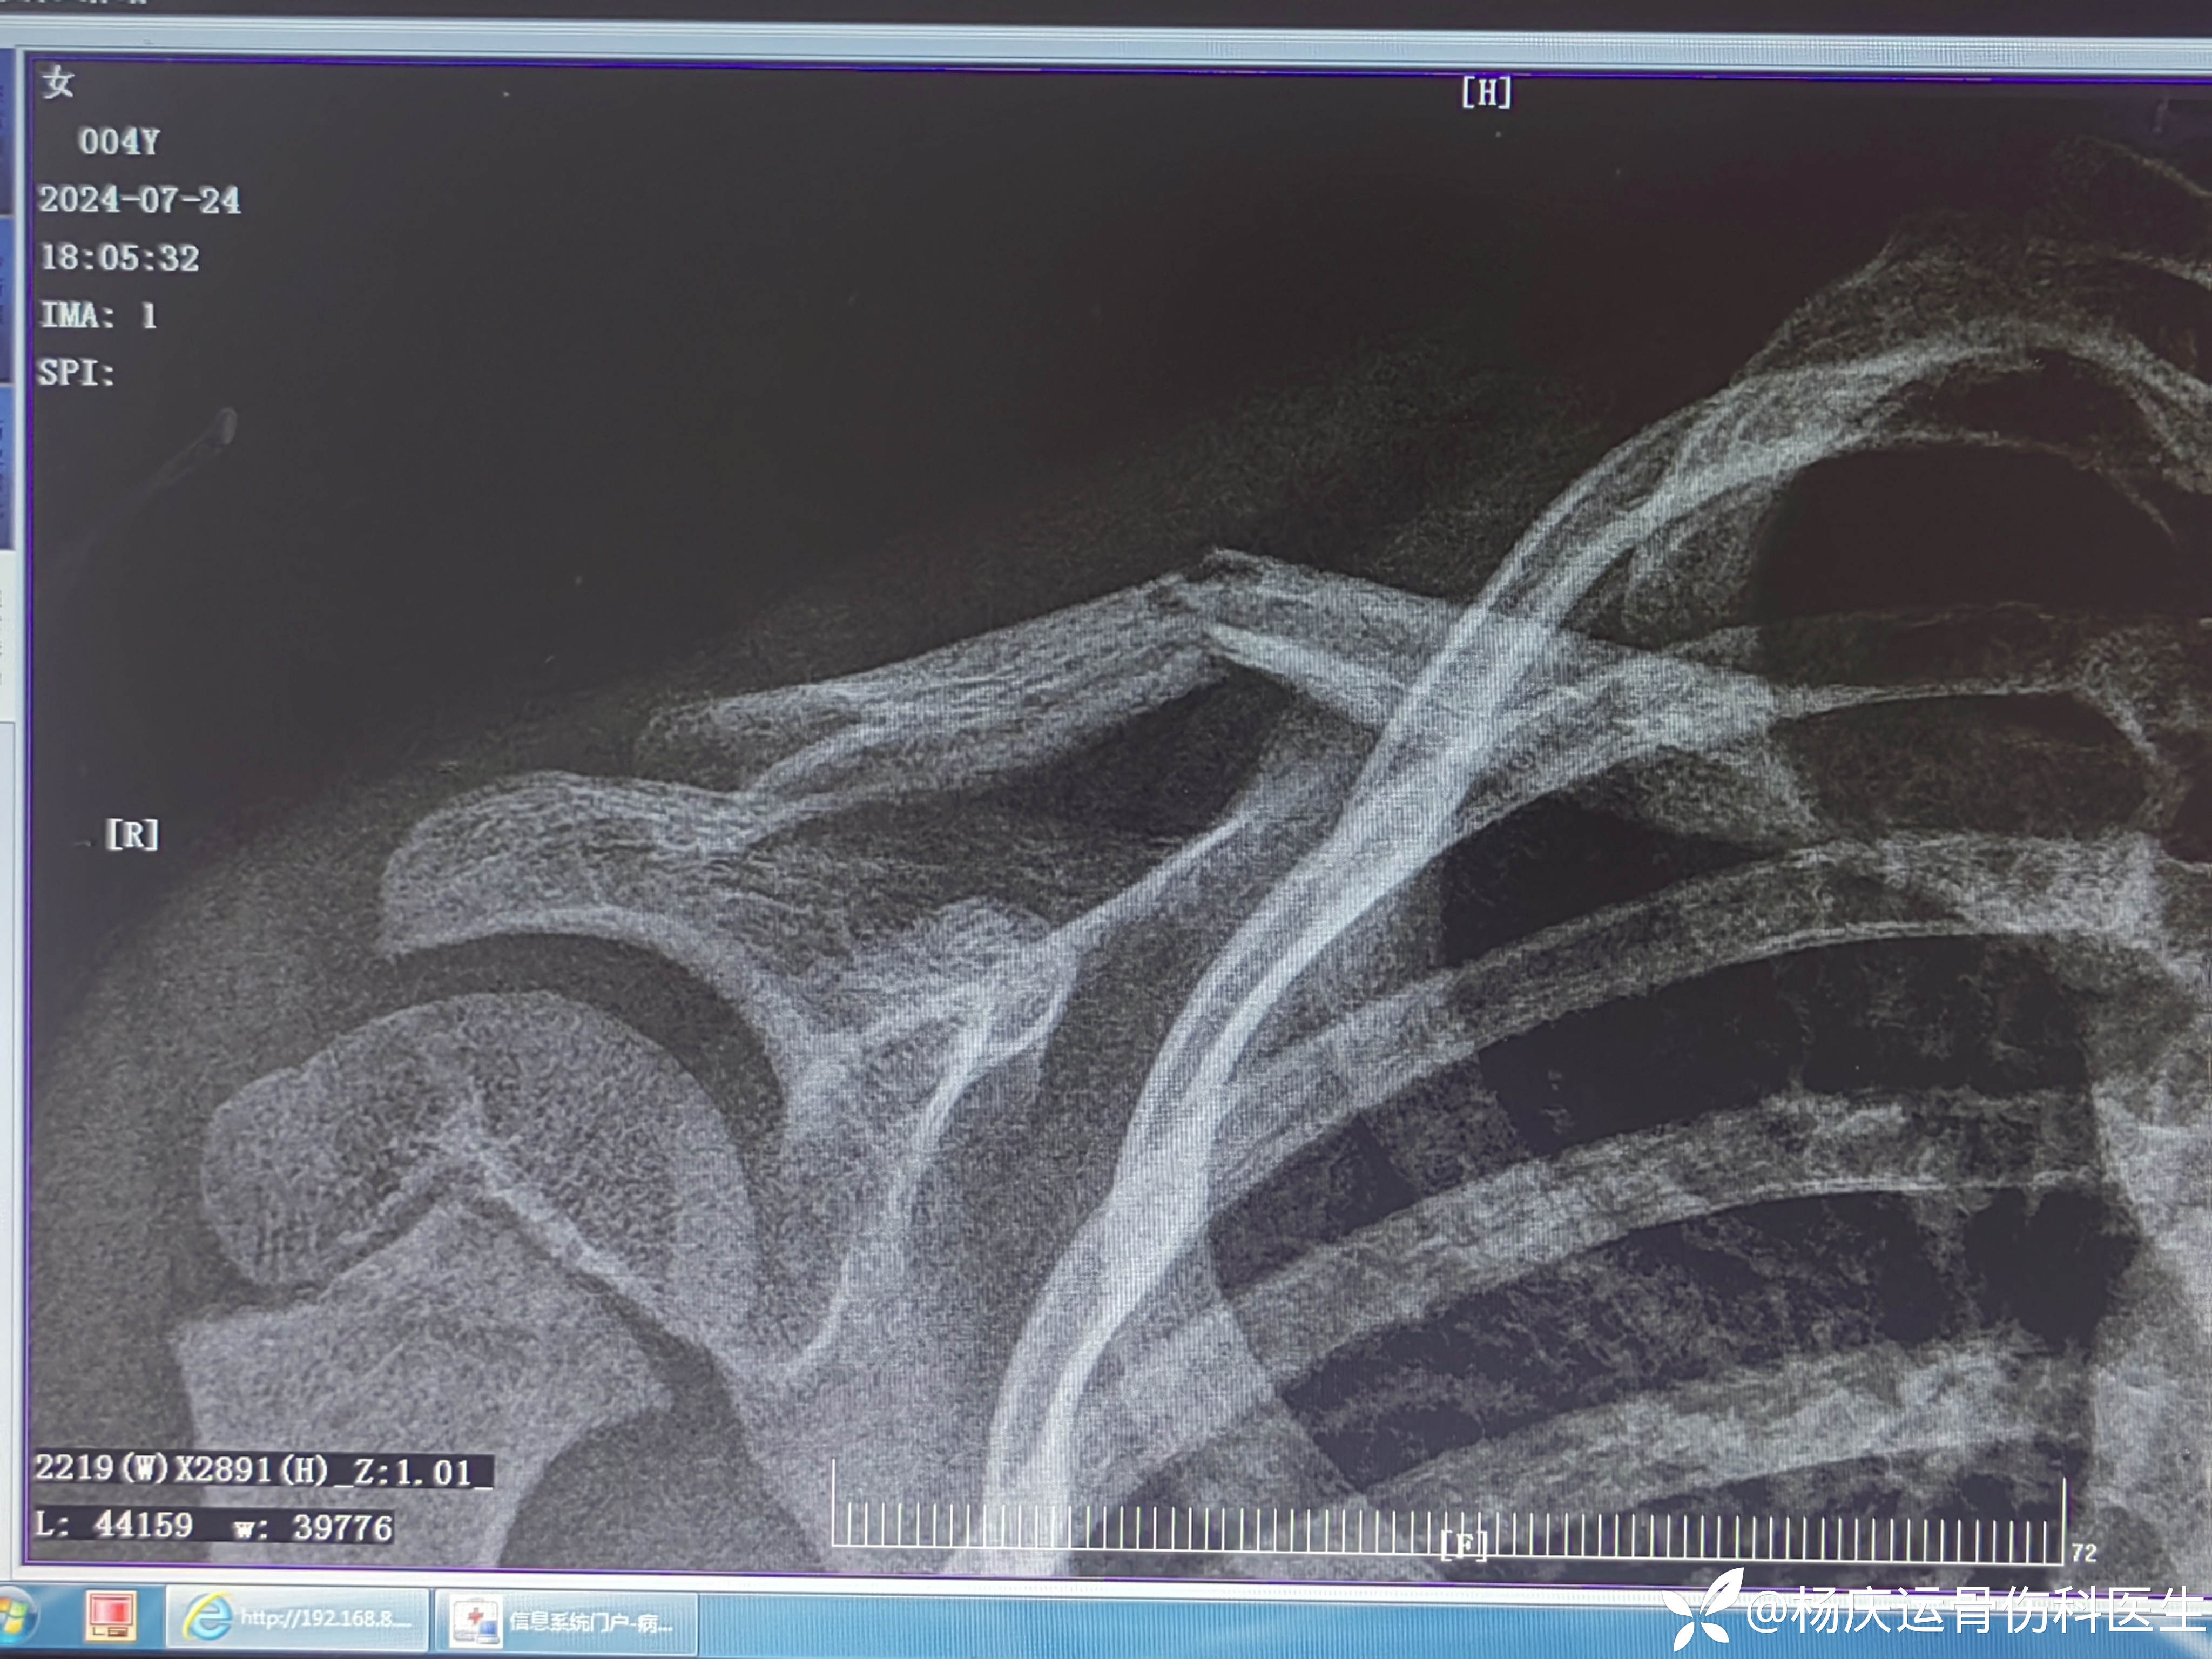

患者万,女,4岁,右肩外伤肿痛畸形活动受限2小时。